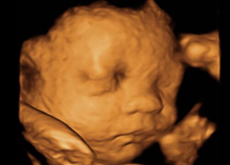

很多準(zhǔn)媽媽都發(fā)現(xiàn),四維彩超上寶寶的鼻子都特別大,還很扁,于是就開始擔(dān)心寶寶的鼻子是不是又大又扁,擔(dān)心寶寶長(zhǎng)得不好看怎么辦。四維胎兒鼻子很大是怎么回事呢?...

四維彩超它是目前最先進(jìn)的彩超設(shè)備,說起四維彩超的功能和作用,相信只要是懷孕過的媽媽們一定都十分清楚,四維彩超不僅可以檢測(cè)篩查胎兒畸形,而且它還可以很全面的檢測(cè)出寶...